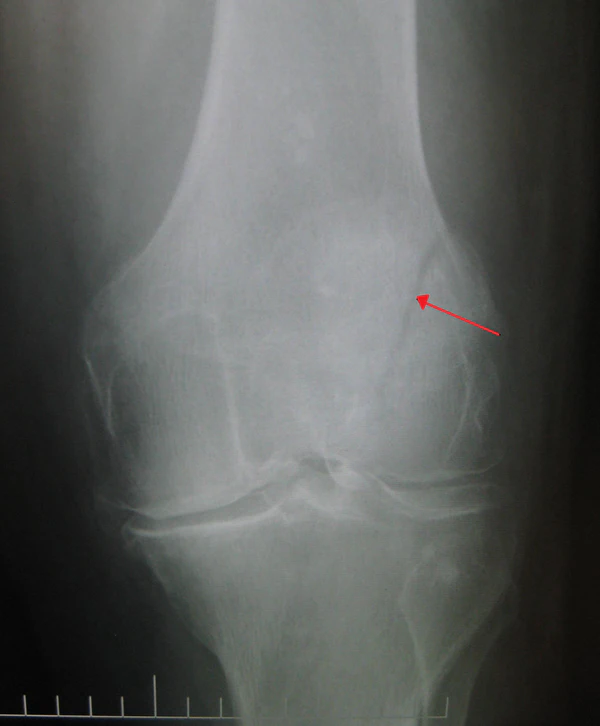

- Рентгенография коленного сустава двух проекциях

- Компьютерная томография

- Двудольный надколенник[2]

Выполнение контрольной рентгенографии через 1,5, 3, 4, 8—12 месяцев. На основе результатов контрольных рентгенографических исследований необходимо проконсультироваться с клиникой, где была проведена операция, и учесть рекомендации хирурга, который её проводил, относительно дальнейшего лечения[1].